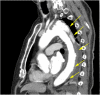

Background: Helicobacter cinaedi is rarely identified as a cause of infected aneurysms; however, the number of reported cases has been increasing over several decades, especially in Japan. We report three cases of aortic aneurysm infected by H. cinaedi that were successfully treated using meropenem plus surgical stent graft replacement or intravascular stenting. Furthermore, we performed a systematic review of the literature regarding aortic aneurysm infected by H. cinaedi.

Case presentation: We present three rare cases of infected aneurysm caused by H. cinaedi in adults. Blood and tissue cultures and 16S rRNA gene sequencing were used for diagnosis. Two patients underwent urgent surgical stent graft replacement, and the other patient underwent intravascular stenting. All three cases were treated successfully with intravenous meropenem for 4 to 6 weeks.